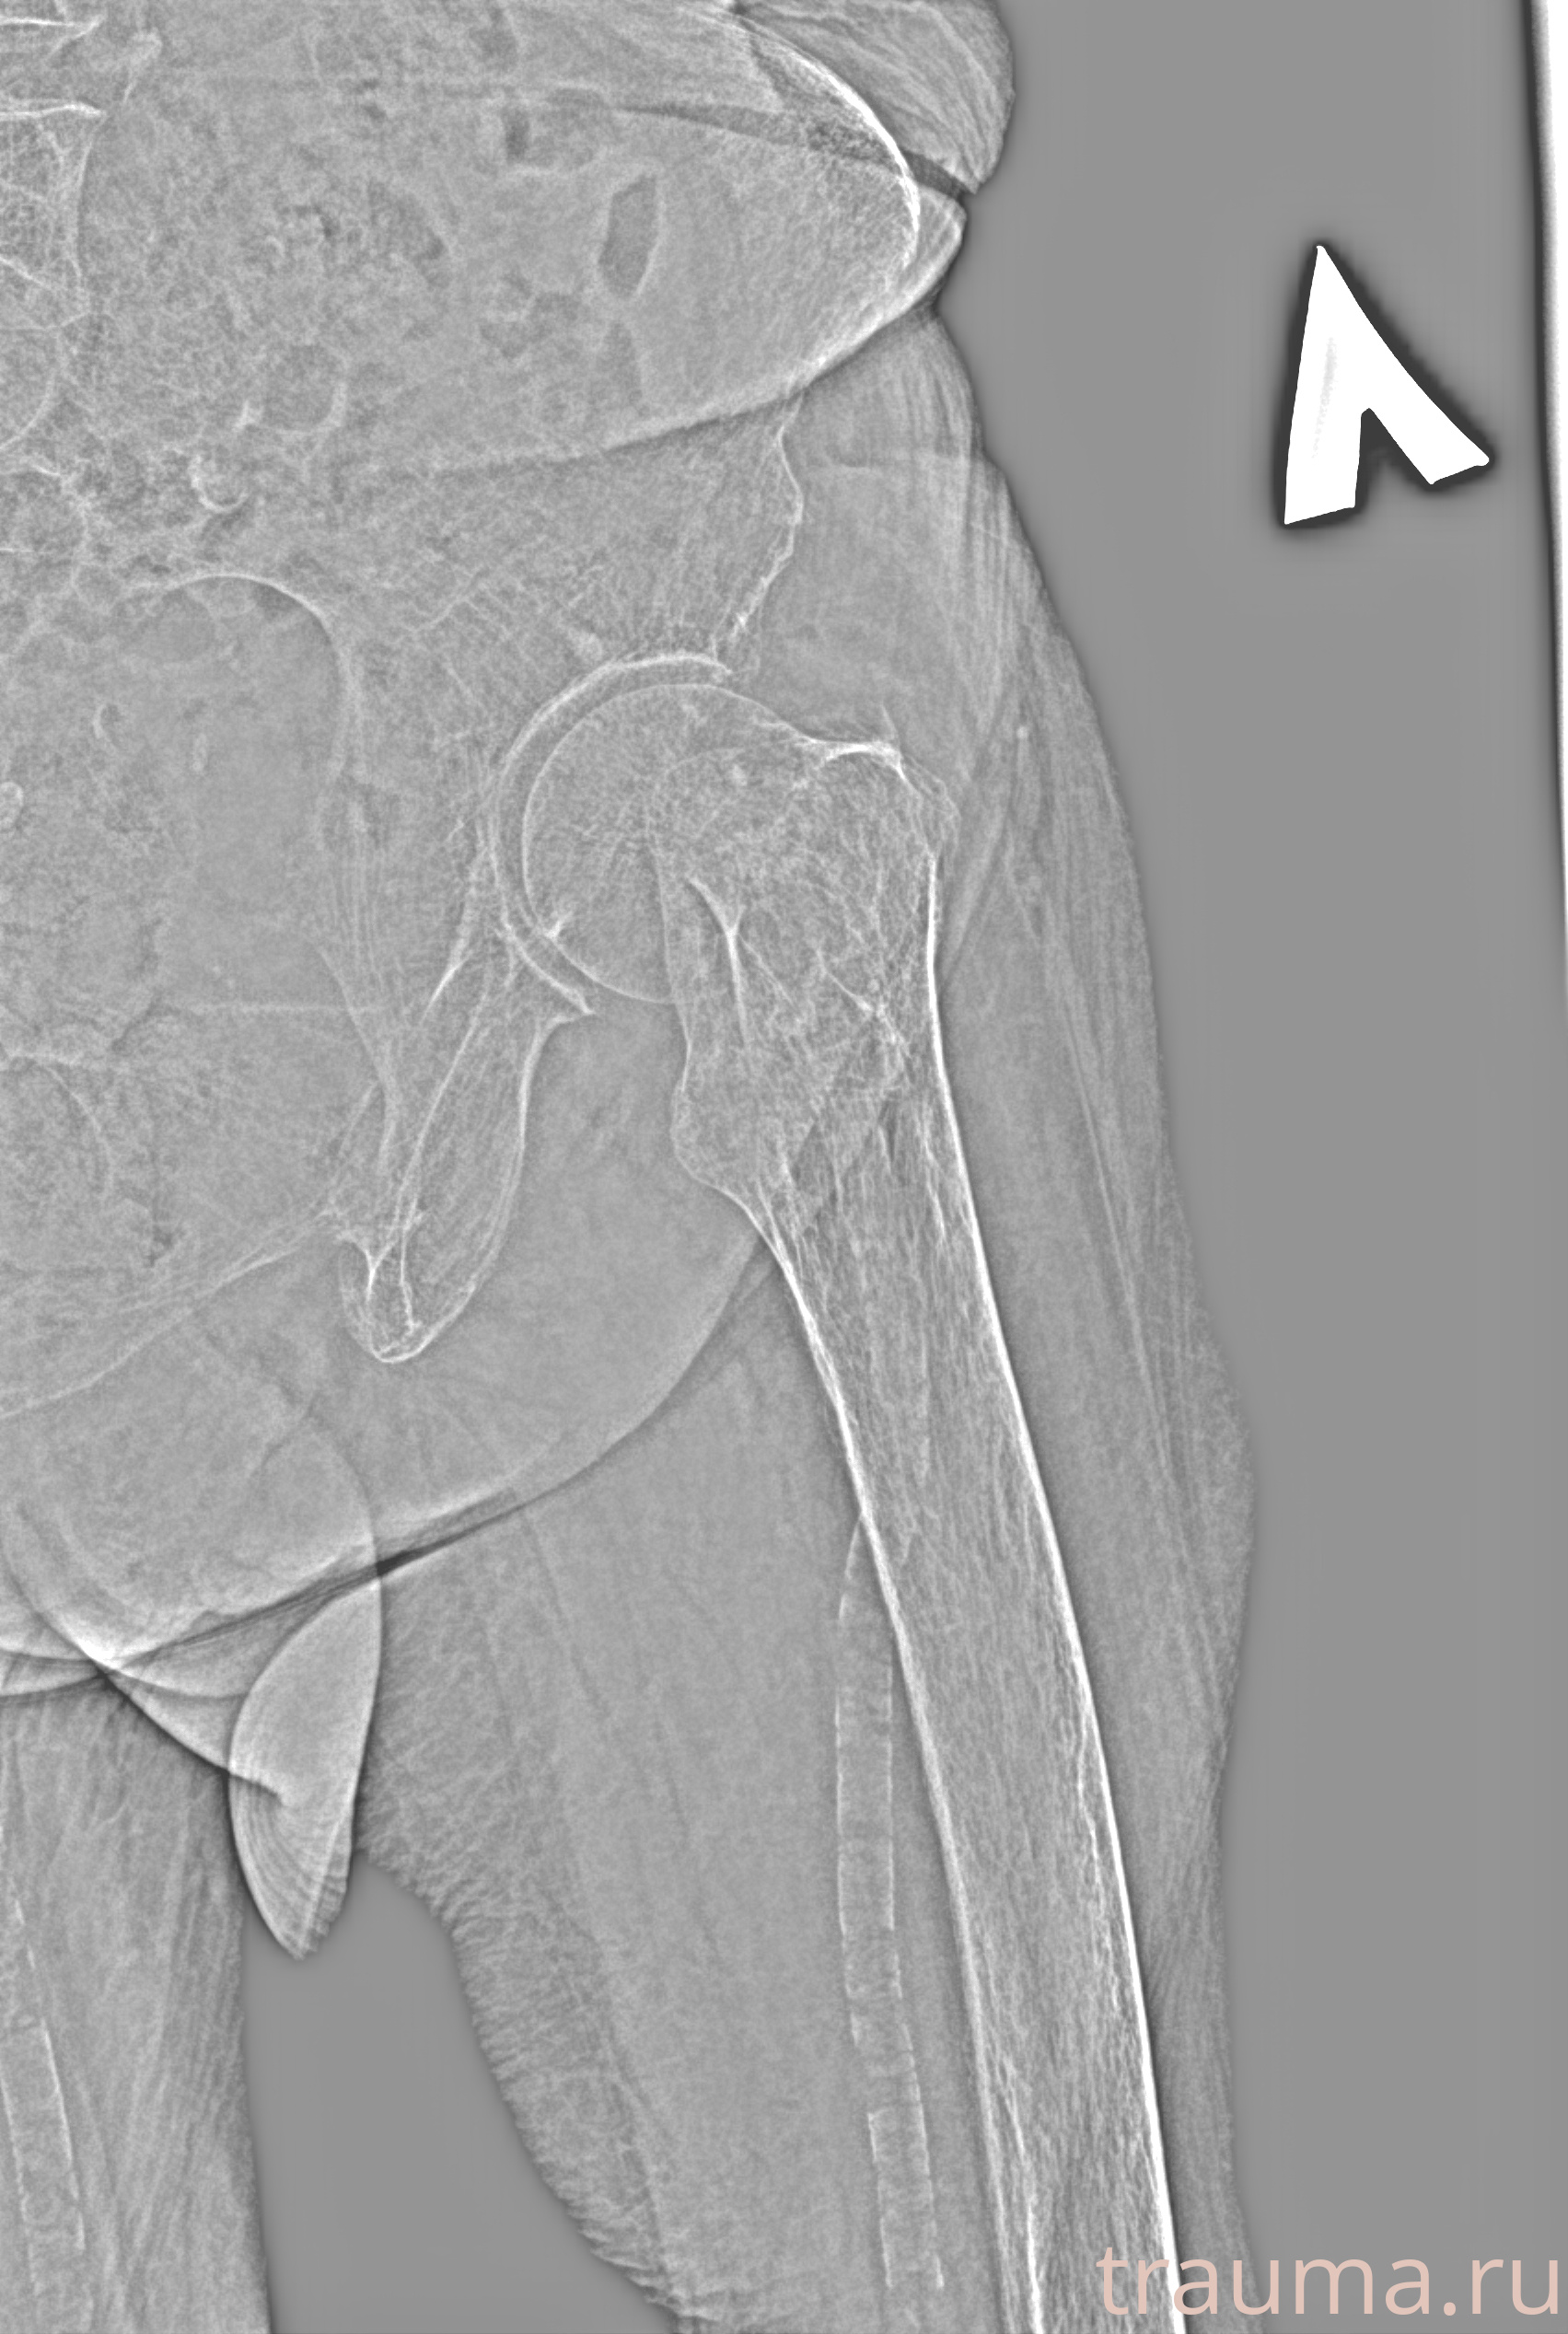

Рентгенограммы

Рентген на дому: по вашему адресу приезжает врач-рентгенолог, травматолог-ортопед с мобильным рентгеновским аппаратом, проводит диагностику травмы или заболевания, делает необходимые рентгенограммы, дает рекомендации по дальнейшему лечению. Получить качественные снимки в домашних условиях возможно благодаря уникальной методике, разработанной МосРентген Центром для института  Склифосовского